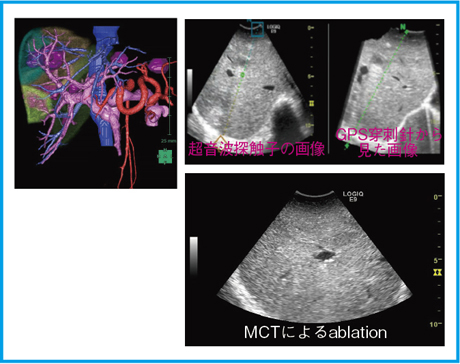

日本超音波医学会第85回学術集会 ランチョンセミナー13 新しいvolume Navigationによる肝癌治療支援 Virtu Traxと手術支援 青木 武士 昭和大学消化器 一般外科准教授 Geヘルスケア ジャパン株式会社 Innavi Suite

第一回jstアカデミー 昭和大学消化器 一般外科のブログ